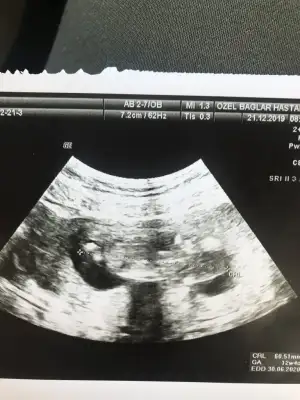

Merhaba bayanlar ben yine doktora gittim ama öğrenemedik cinsiyeti. Bu da son usg. 12h5d

Eklentiler

• IMG_20191221_171735.webp